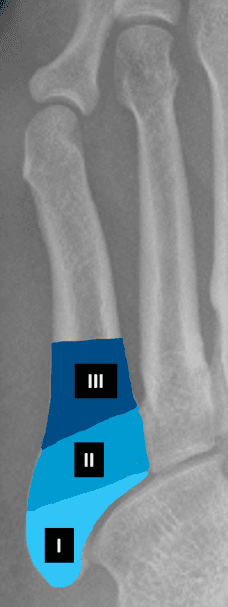

Mellomfotsbeinene, metatarsene, er beinene som går fra fotroten og frem til det innerste leddet til tærne. De fem beinene nummereres fra 1 til 5 - metatars 1 er på stortåsiden. Hvert bein er en rørknokkel med to tykkere ender og et slankere skaft. Enden lengst ut benevnes caput (hodet) og enden lengst inn benevnes basis. De to endene er også leddhoder som danner ledd med tå-beina (MTP-ledd) og med fotrotsbeina (CMT-leddene).

Jones brudd i 5. metatars

Denne bruddtypen er mindre vanlig enn tennisbrudd, men er mer problematisk å behandle. Det er et tverrbrudd ca. 1,5-3 cm lengre ut i metatarsen, det vil si i skaftet til 5. metatars. Bruddet oppstår ofte ved indirekte skade (under trening). Feilstillingen ved dette bruddet tenderer til å øke under vektbelastning. Det er ganske vanlig at bruddet ikke gror, noe som kan skyldes at man har belastet foten for tidlig. Behandlingen er som regel støvelgips og avlastning i 7 uker. Pasienter med dette bruddet utvikler ofte (35-50%) vedvarende manglende tilheling og trenger bentransplantasjon og intern fiksasjon (pinne, streng eller skrue). Noen velger operativ avstiving fra starten av hos profesjonelle idrettsutøvere. Ved manglende tilheling gjøres operasjon der man bruker beintransplantat.